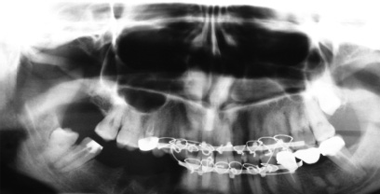

С появлением дентальной имплантации стало возможным отказаться от протезирования съемными и частично съемными протезами. В настоящее время, в предоперационном периоде, нами используется метод дентальной имплантации для замещения дефектов зубных рядов и восстановления прикуса больного, что дает возможность полного шинирования зубного ряда и получения стабильной фиксации во время хирургического вмешательства по поводу ложных суставов нижней челюсти (рис.1-5).

Рис.1.